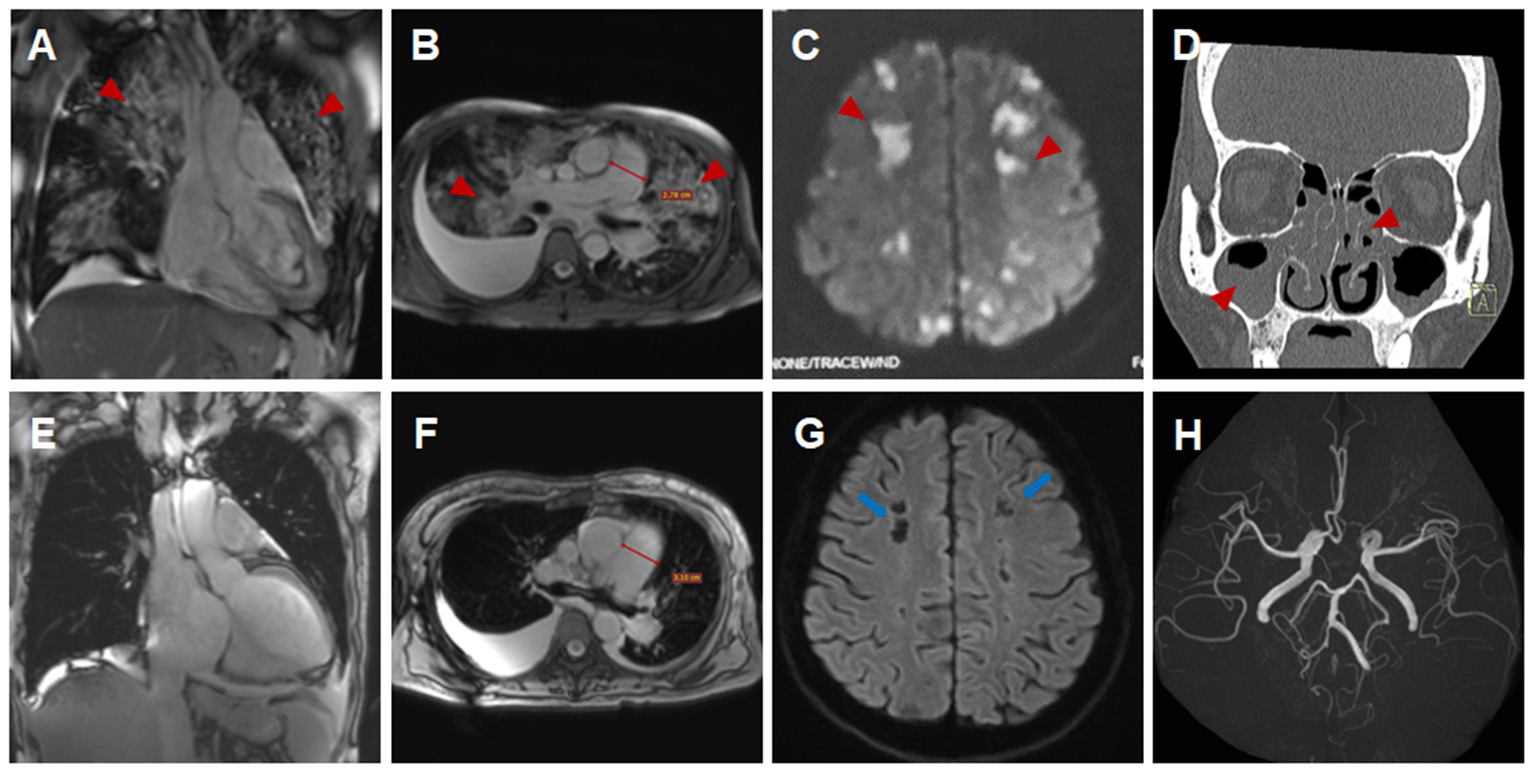

Figure 1

Imaging findings of eosinophilic granulomatosis with polyangiitis (A–D,H) Imaging findings during the initial hospitalization (A,D, coronal view; B,C,H, transverse view). Multiple patchy consolidations of both lungs (A,B, triangular arrows) on CMR images, multiple acute cerebral infarctions (C, triangular arrows) with no obvious cerebrovascular stenosis (H, triangular arrows) on brain MR images and sinusitis and nasal polyps (D, triangular arrows) on reconstructed CT images. (E–G) Imaging findings during the subsequent hospitalization (E, coronal view; F,G, transverse view). Significantly absorbed multiple lesions of both lungs (E,F), the pulmonary hypertension with increased diameters of pulmonary trunk from 28 mm (B) to 32 mm (F) and multiple encephalomalacia (G, long arrows).

A 44-year-old female patient presented to our hospital with a 1-month history of dizziness, fatigue, chest tightness, and shortness of breath. She also had ecchymosis of the lower legs. The patient presented with a 10-year history of asthma, sinusitis, and nasal polyps (Figure 1D). Electrocardiograph (ECG) demonstrated QS waves in leads V2-V3, ST segment depression in leads V5-V6, and T-wave inversion. Blood pressure was 90/62 mmHg, pulse was 112 beats/minute. Laboratory findings (Table 1) showed increase in the percentage of eosinophils (47.8%), erythrocyte sedimentation rate (ESR) (32 mm/H), C-Reactive protein (CRP) (24.70 mg/L), N-terminal pro-B-type natriuretic peptide (NT-proBNP) (12,045 pg/mL), and troponin I (1.760 ng/mL). Diagnostic work up revealed negative anti-nuclear antibodies (ANA), ANCA, anti-MPO antibodies, and rheumatoid factor. The patient's renal function was normal and there was no evidence of blood infection. Diffusion-weighted imaging of the brain magnetic resonance imaging (MRI) revealed multiple acute cerebral infarctions (Figure 1C) with no obvious cerebrovascular stenosis on magnetic resonance angiography (MRA) (Figure 1H). Chest CT and Cardiac magnetic resonance (CMR) localizing images showed multiple patchy consolidations of both lungs and bilateral pleural effusion (Figures 1A,B). After completing a series of examinations and multi-disciplinary discussions, the patient met the inclusion criteria of the American College of Rheumatology 1990 criteria for the classification of EGPA (3). Transthoracic echocardiography showed numerous deposits in the mural left ventricular (LV) endocardium, obliteration of the apical portion of the left ventricle, enlarged left atrium, moderate pulmonary hypertension [the estimated systolic pulmonary artery pressure (eSPAP) was 46 mmHg] and a small pericardial effusion. 18F-FDG PET-CT showed accumulation of FDG in the lungs and myocardium. CMR was used to assess the cardiovascular involvement which was performed on a 3.0 T MRI at 8 days after admission, confirming Löffler endocarditis (endocardial thickening, edema and enhancement) with LV thrombus on cine, perfusion, and LGE images (Figures 2A–F, Supplementary Videos 1–6), LV volume enlargement and mildly reduced LV systolic function, normal right ventricular volume, and function (Table 2, Supplementary Videos 1–4).